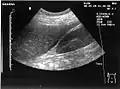

Ultrasonographic view of the abdomen demonstrating fluid within Morison's pouch -